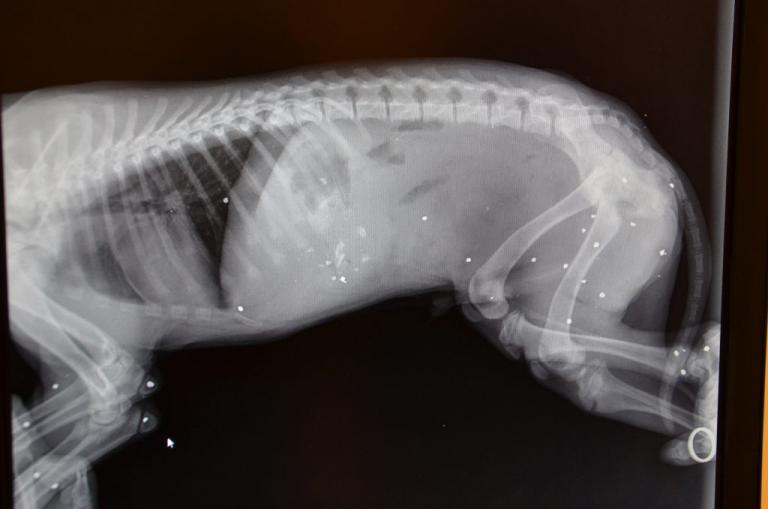

Το θετικό της υπόθεσης είναι πως με τη συνδρομή των αστυνομικών του τμήματος Τεμπών το άτυχο ζώο μεταφέρθηκε άμεσα στη Λάρισα για να του παρασχεθούν οι πρώτες βοήθειες από κτηνίατρο, με αποτέλεσμα αυτή τη στιγμή να νοσηλεύεται εκτός κινδύνου.